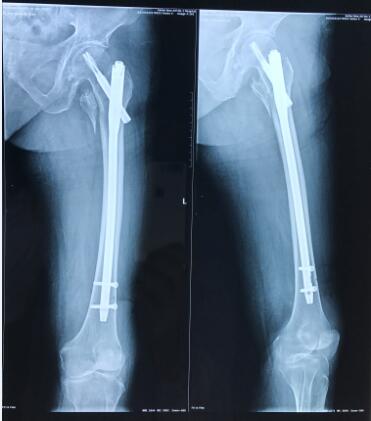

祖奶奶93岁高龄,因不慎摔伤致左侧股骨粗隆间骨折,伤后前往附近医院就诊。因患者高龄,合并糖尿病,手术风险极高,该院放弃治疗,转入我院关节与显微修复外科就诊,我科胡孔足主任术前结合患者综合情况,联合内科、麻醉科会诊,控制糖尿病,结合神经阻滞麻醉,采用股骨近端防旋髓内钉(PFNA)闭合复位内固定方案,以最小的创伤获得良好的固定。手术顺利,术后患者恢复良好。术后两天即可扶拐下地行走,迅速恢复生活自理能力。老年股骨粗隆间骨折由于内固定手术要求高,失败率较高,很多医院建议放弃内固定术,采用人关节置换术。但是人工关节置换术存在手术损伤大,术后容易脱位等问题,患者恢复仍然困难。相对于人工关节置换手术,闭合复位髓内内固定具有创伤小,出血少,对髋部肌群未造成明显干扰的特点,降低了感染风险,避免了人工关节脱位、人工关节翻修等棘手问题,经过康复训练后可以很好恢复功能。